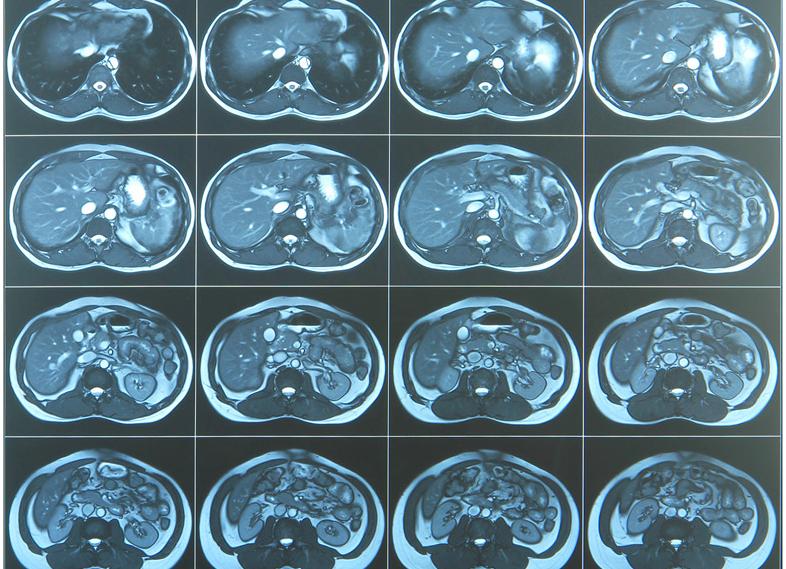

Диагностика кишечника при мрт брюшной полости недоступна при проведении обследования классическим способом. Для верификации патологических нарушений требуется исследование с контрастом.

Воздушные ткани магнитно-резонансная томография не визуализирует. Качественная диагностика возможна только водосодержащих органов. Суть анализа базируется на испускании атомами водорода радиочастот, которые регистрируются датчиками и преобразуются в графическое изображение.